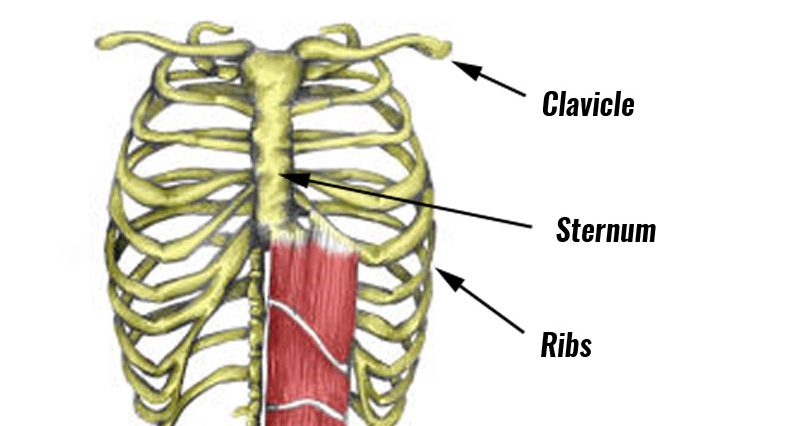

A broken rib typically causes sharp pain. To diagnose a rib injury, it’s best to see a medical professional who can look at your injuries with professional tools and technology. You may also feel or hear a crack or pop when the.

Sometimes, you may be able to feel a break in your rib by rubbing your finger over the rib. If you have a tender area on your ribs that hurts with every breath, you may have a broken rib. If you heard cracking during the injury or you hear or feel cracking when you move or.

Take slow, deep breaths and cough regularly to expand your lungs, use an incentive spirometer if asked to do so, get up and move around when you’re not sleeping,. When visiting your doctor, they will most likely be able to diagnose your injury simply by pushing on your chest and doing a physical exam. The pain you feel with a broken rib typically occurs or even worsens when you: